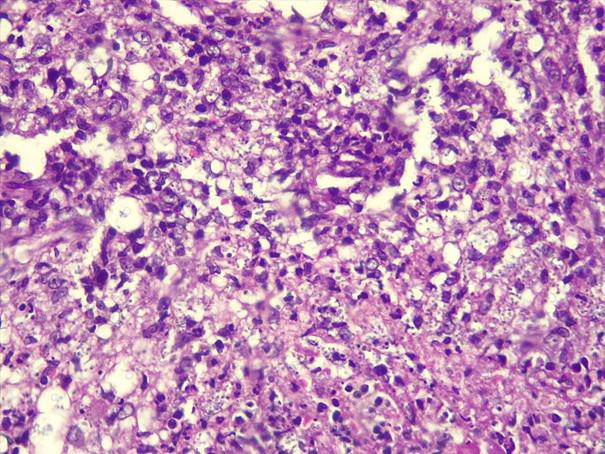

*Case 3 : Pr Modupeola Samaila/ Dr Rimamscep Ifusumu

email: mamak97@yahoo.com

Clinical detail: Female, 38 years. Orbital cystic tumour of 2 years duration.

Clinical diagnosis is orbital tumour query mucormycosis.

Please, consult the virtual slides of Case 3 below.